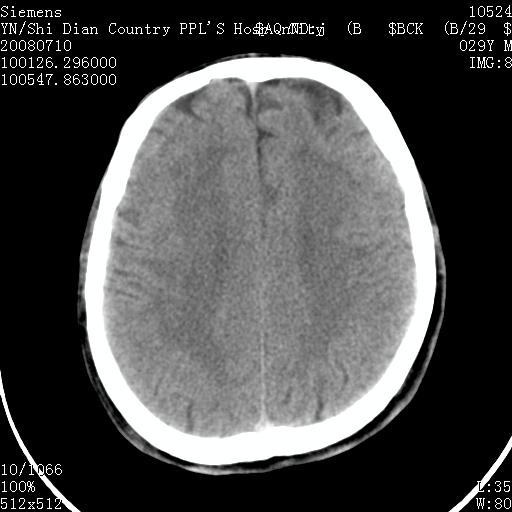

以下是引用pujunzhi在2008-7-10 13:06:00的发言:[br]透明间隔腔

以下是引用随光逐影在2008-7-10 15:19:00的发言:[br]1)考虑左侧尾状核钙化。2)透间隔间腔与vergae腔并存。

以下是引用卜一在2008-7-10 16:43:00的发言:[br]1)考虑左侧尾状核钙化。2)透间隔间腔形成。支持!